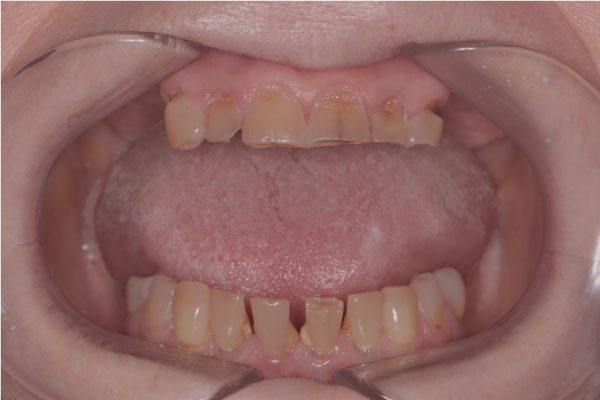

Имплантация зубов: фото «До» и «После»

Фото ДО

Фото ПОСЛЕ

All-on-4